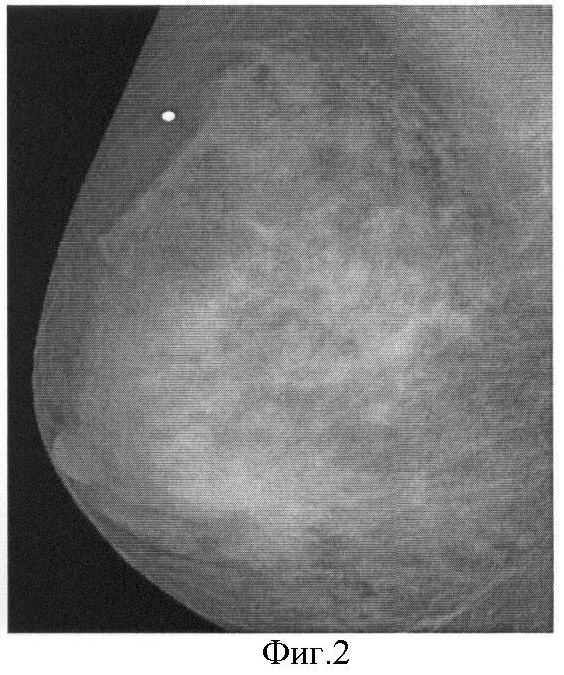

На фиг.2 представлен пример маммограммы, полученной данным способом, заимствованный в работе (см. Radiology, 1998; p.p.209, 238, Lewin JM, Hendrick RE, D’Orsi CJ, et al. Clinical evaluation of a full field digital mammography prototype for cancer detection in a screening setting-work in progress).

Несмотря на повышение резкости изображения, по сравнению с традиционной маммограммой, онкологическая опухоль и микрокальцинаты проявляются не достаточно резко.

На фиг.1 представлена традиционная молочная железа, на которой прямоугольниками выделены области здоровой ткани (1) и с онкологической тканью (2); на фиг.2 – маммограмма, полученная при использовании способа прототипа; на фиг.3 – зависимость отношения и разности массовых коэффициентов полного поглощения от эффективного атомного номера; на фиг.4 – традиционная маммограмма; на фиг.5 – визуализация распределения эффективного атомного номера; на фиг.6 – традиционная маммограмма (ТМ), эффективный атомный номер (Z), плотность ( ) и их произведение ( Z) онкологической опухоли; на фиг.7 – микрокальцинаты при смещении исходных снимков; на фиг.8 – визуализации распределения идентифицируемого эффективного атомного номера при уменьшении разности энергий излучения; на фиг.9 – визуализации распределения эффективного атомного номера онкологической опухоли при нелинейных преобразованиях исходного распределения числа зарегистрированных фотонов на разной энергии; на фиг.10 – визуализации распределения микрокальцинатов при нелинейных преобразованиях исходного распределения числа зарегистрированных фотонов на разной энергии.